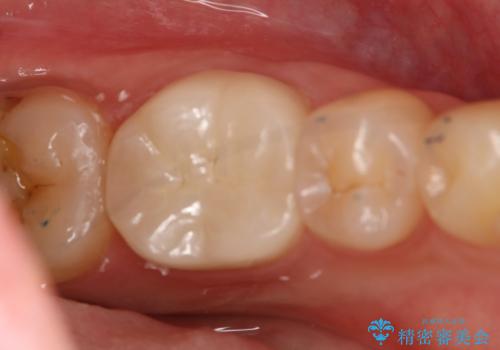

精密根管治療を行なったことで病巣は消失し、腫れや痛みは再発することなく経過は良好です。

被せ物はフルジルコニアクラウンを選択されました。